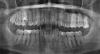

Pinktooth Опубликовано 24 августа, 2013 Автор Поделиться Опубликовано 24 августа, 2013 Благодарю за Ваши ответы! Можно поподробнее о том как лечатся подобные случаи?Какие могут быть последствия лечения форфенаном? Обратимо ли это? Вы снимок выложите, тогда совет будет, относительно лечения... На форуме нет сторонников (ну либо единицы) этого метода леченияА какой метод лечения применяют в таком случае?Прикладываю снимок (распечатку), надеюсь сможете на нём разглядеть. Там уже уже почищены кариозные поражения и удалены два нерва, третий нерв - склерозирован. Форфенану нет и еще раз нет! Выкладывайте рентгеновский снимок зуба. Если не форфенан то что? Является ли хорошей альтернативой AH Plus? Ссылка на комментарий

juli63 Опубликовано 25 августа, 2013 Поделиться Опубликовано 25 августа, 2013 Судя по снимку, на подходе еще несколько зубов. Ссылка на комментарий